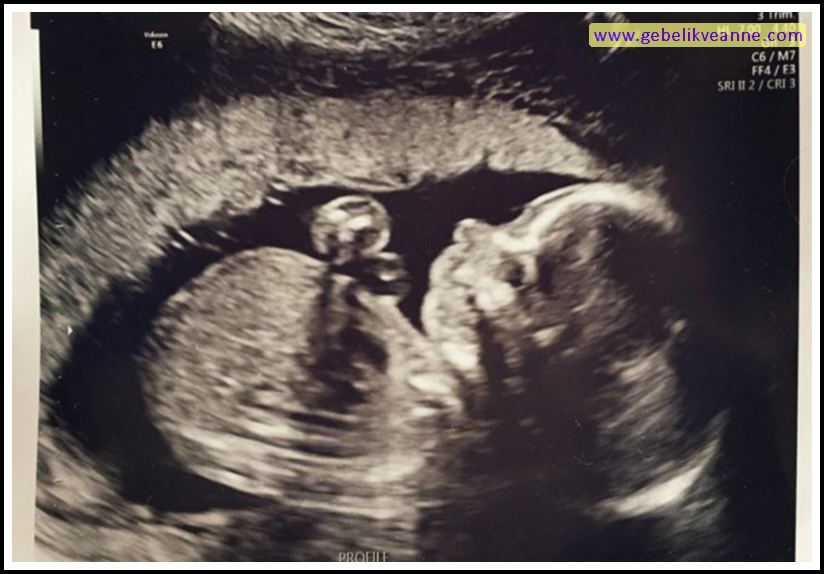

20 Haftalık Gebelik (Hamilelik) Ultrason Görüntüleri

Source: www.gebelikveanne.com

20 haftalık gebelik ve 4d. 8 haftalık hareket eden fetus görüntüsü. 20 haftalık gebelikte bebeğin boyu ve kilosu.